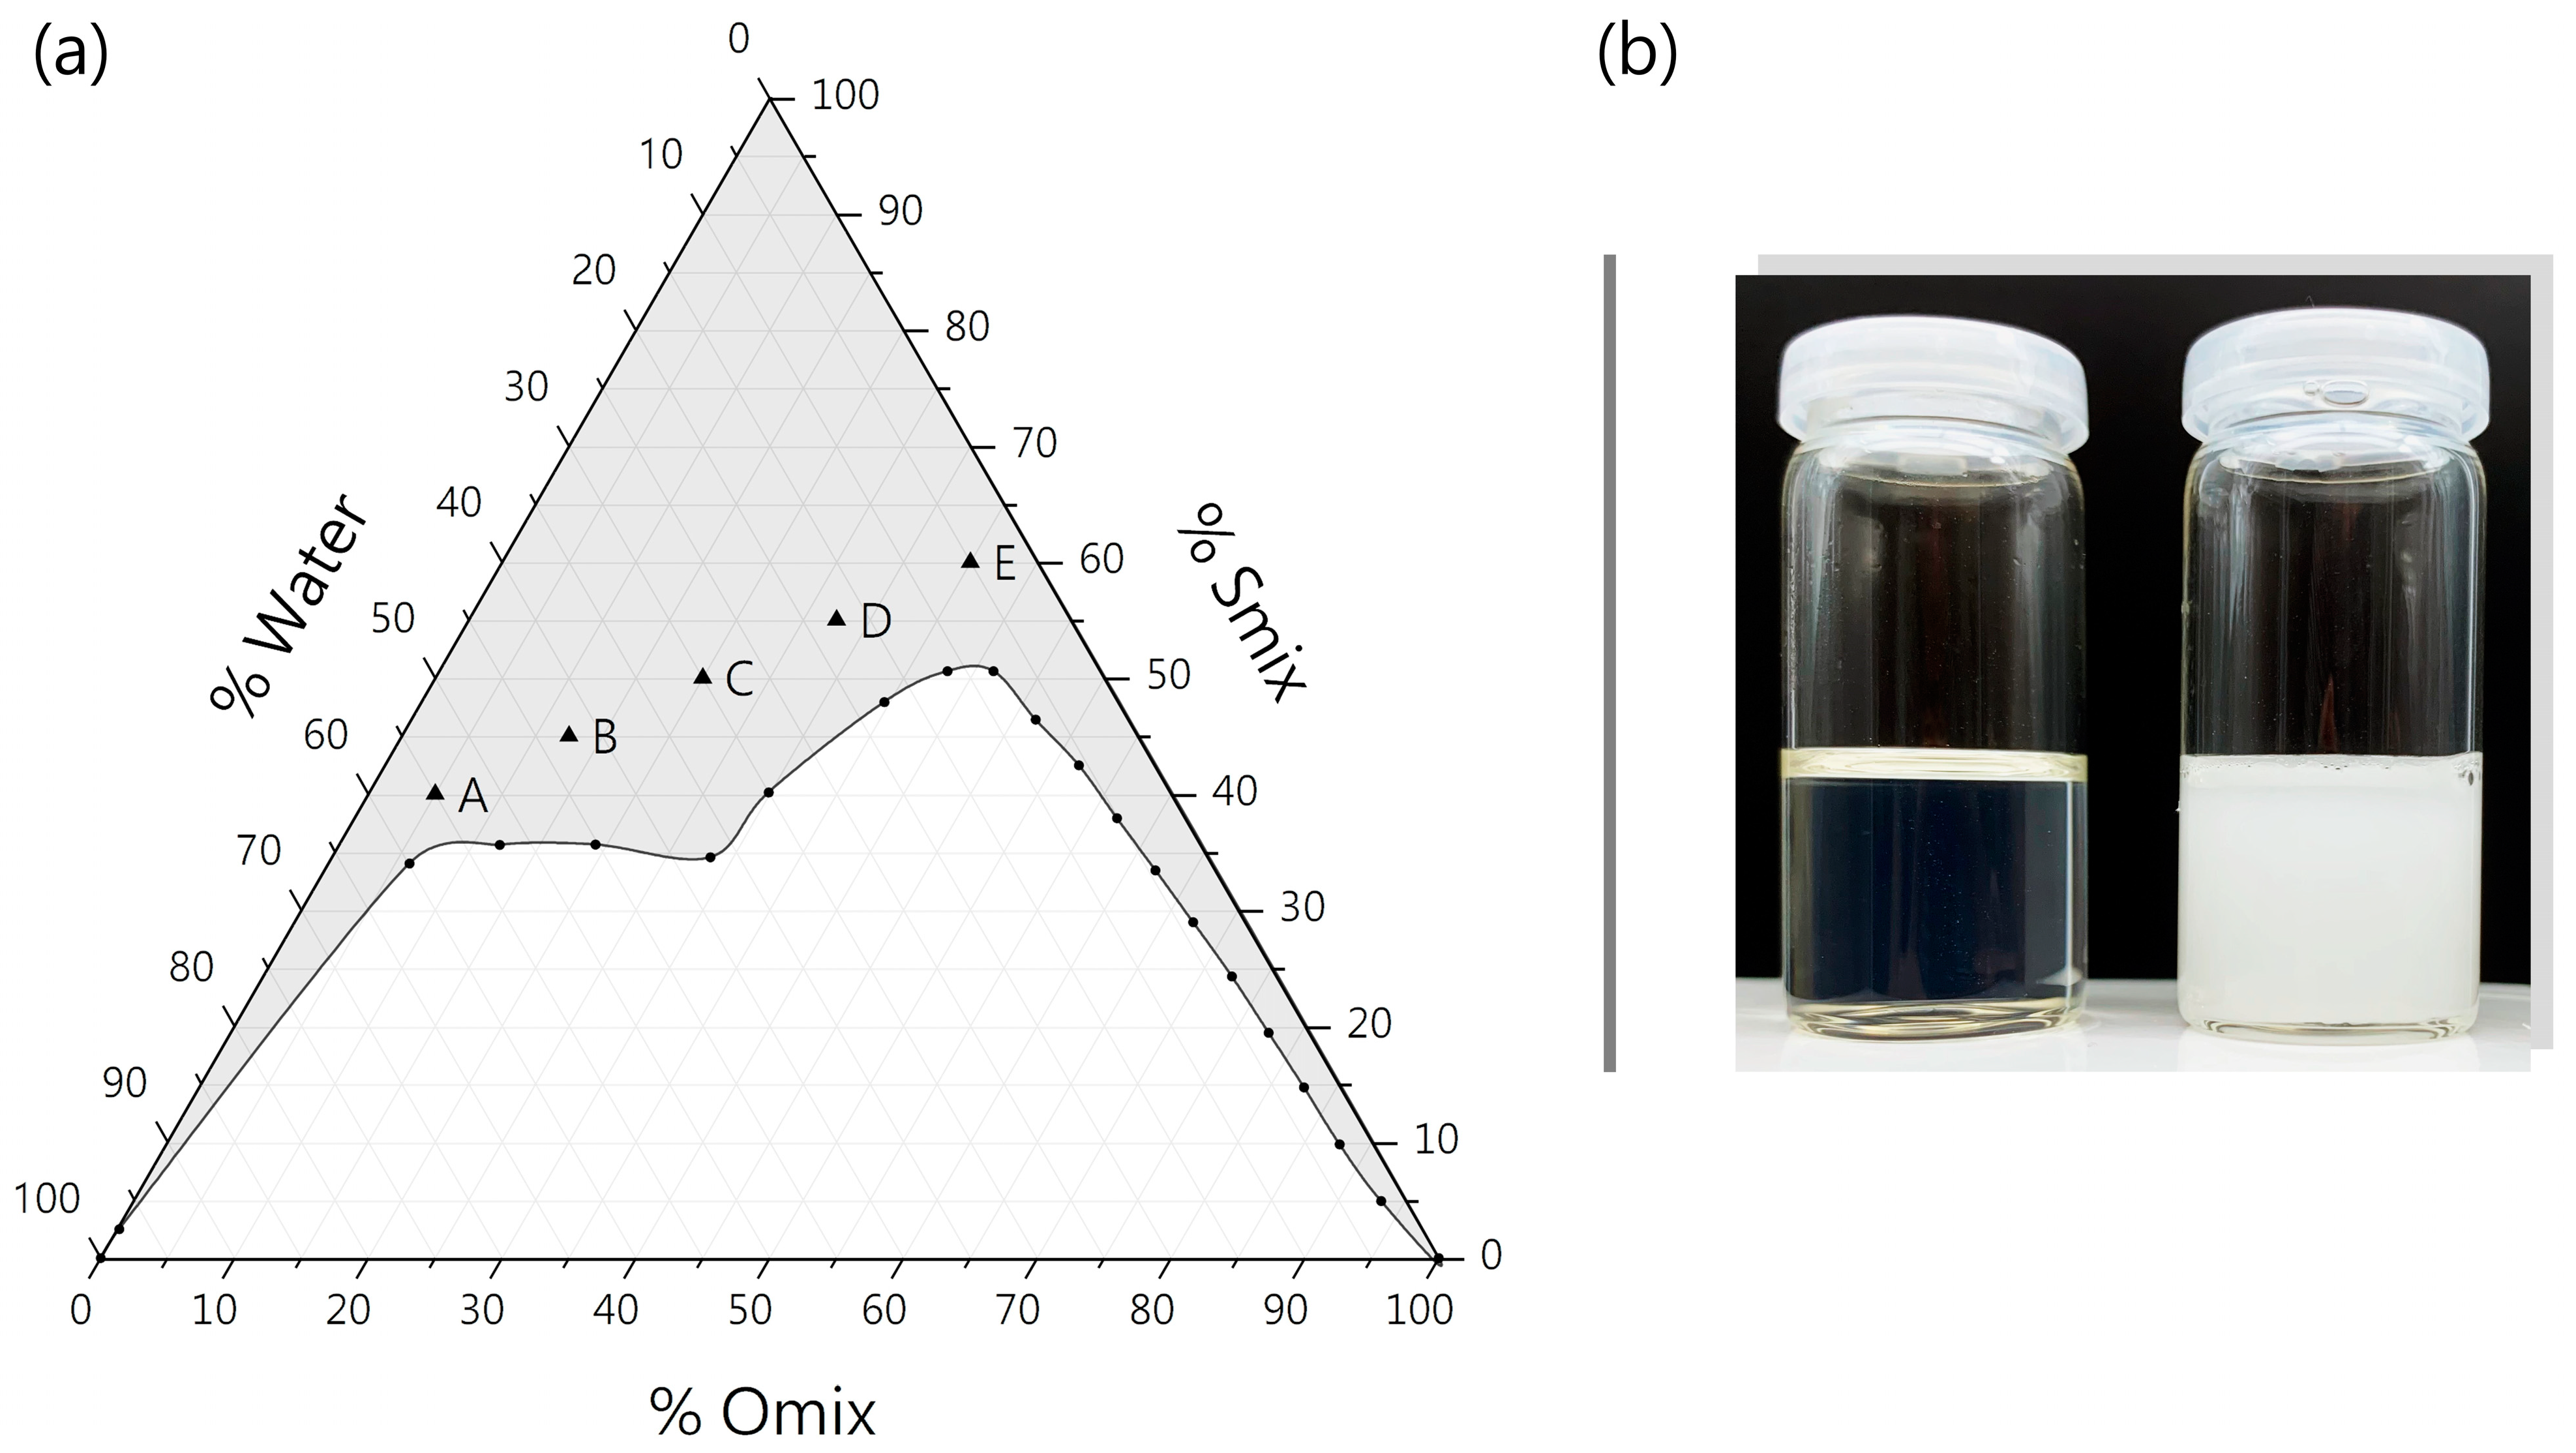

3.1.1. Pseudo-Ternary Phase Diagram

3.1.2. Electrical Conductivity and ME Microstructure